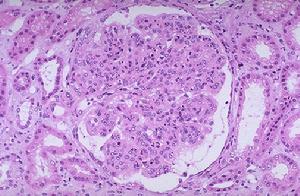

光鏡下,Ⅰ型典型的病變是,瀰漫性系膜細胞和系膜基質重度增生,沿內皮細胞和基底膜之間長入或插入(mesangialinterposition),使毛細血管壁增厚,鍍銀染色或PAS染色基底膜呈雙層(doublecontour)或多層狀改變,這是由於系膜基質插入造成的。由於系膜細胞和系膜基質重度增生,系膜區域擴大導致腎小球呈明顯的分葉狀。Ⅱ型膜增生性腎小球腎炎也呈現這些病變,但與Ⅰ型相比,系膜增生輕,腎小球分葉狀結構不明顯。

免疫螢光Ⅰ型膜增生性腎小球腎炎顯示IgG和補體C3呈顆粒狀和團塊狀沉積於毛細血管壁和系膜區。Ⅱ型膜增生性腎小球腎炎顯示大量補體C3沉積於毛細血管壁和系膜區。

電鏡下系膜細胞和系膜基質增生伴系膜插入,即增生的系膜細胞和系膜基質插入到基底膜和內皮細胞之間。系膜基質和基底膜形態相似,因而看上去似有兩層或多層基底膜,這就是光鏡下所見的雙層或多層的形態,一層是原有基底膜,另幾層是插入到內皮細胞和基底膜之間的系膜基質。腎小球內可見電子緻密物。Ⅰ型大量電子緻密物位於基底膜內皮側及系膜區域,少量見於上皮下;Ⅱ型電子緻密物的電子密度較Ⅰ型明顯高,沿基底膜緻密層呈帶狀分布。